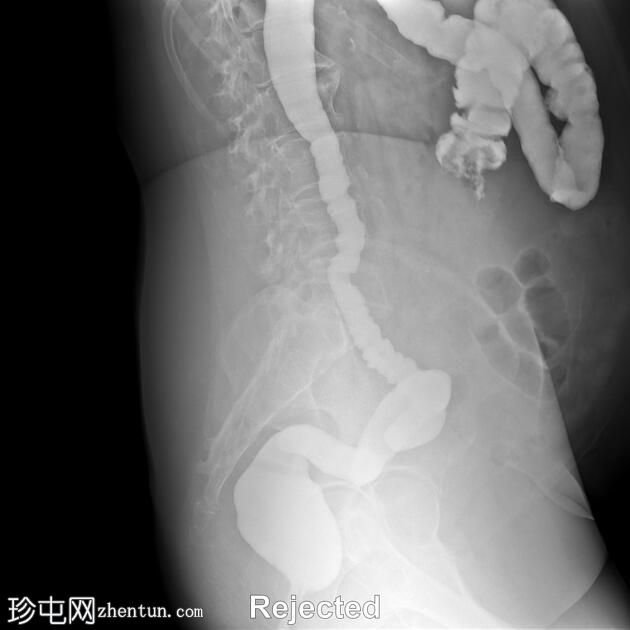

侧位

结肠异常表现包括结肠袋皱襞消失,使其外观模糊,呈铅管样改变。

其他异常表现包括降结肠和乙状结肠肠袢狭窄,以及横结肠和降结肠多处黏膜糜烂(双对比增强图像可见)。

未见肿块或瘘管形成。

升结肠外观正常,结肠袋皱襞完整。